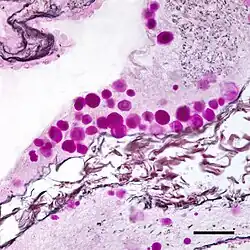

Natural luminescence of corpora amylacea in the lumen of the prostate in ultraviolet light

Natural luminescence of corpora amylacea in the lumen of the prostate in ultraviolet light -